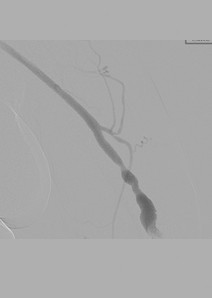

Fistulograma tras la primera pasada con un catéter DVX de AngioJet (N. B.: no se usaron trombolíticos).

Fistulograma tras la segunda pasada con un catéter DVX. Se ha identificado otra estenosis hacia la mitad de la FAV.